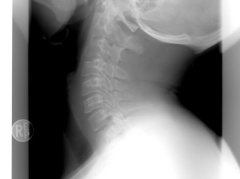

颈椎弹响与突出感需辨明生理性与病理性差异,科学检查和针对性防护可避免误判。日常注意姿势调整、理性对待弹响信号,结合专业理疗改善颈椎稳定性,特别群体需遵医嘱调理。